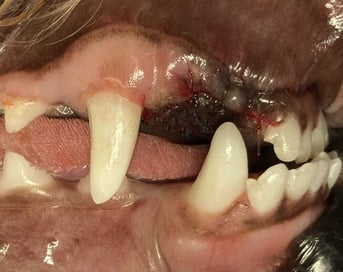

In general, an open extraction technique is advisable for the extraction of the large (especially the permanent) canine tooth. Closed extraction of the canine teeth in young animals can be tempting because the periodontal ligament space is usually wider than in mature patients. Tension-free closure of the site after closed extraction is usually not possible without mobilisation and advancement of the gingiva. Partial closure should be successful to retain the blood clot in the alveolus and support granulation and healing by second intention. Wound breakdown is a possible complication of open extraction techniques, but this can be avoided by appropriate technique ( Figure 1).

The formation of an oronasal fistula after extraction of a maxillary canine tooth or a mandibular fracture during extraction of a mandibular canine tooth remain possibilities, even in young patients. The extraction of deciduous canine or incisor teeth causing trauma to the palate or other soft tissue is the only practical treatment option.

The close proximity of the developing crowns of the permanent teeth is an important consideration. Contact with these structures during the extraction process could cause enamel defects on the permanent canine teeth. It is important to avoid the use of luxators or elevators on the lingual side of the deciduous mandibular canine teeth, and on the mesial aspect of the deciduous maxillary canine, during the extraction procedure.

Radiography is important to confirm the position and degree of resorption of the deciduous teeth to be extracted. Like all deciduous dentition, the tooth roots are extremely long in comparison to the length of the crowns. This is especially dramatic in deciduous canine and incisor teeth: the roots of these teeth could be as much as four to six times the length of the crown. For better visualisation, an open technique is advisable. The complete extraction of the deciduous canines is important in interceptive orthodontic procedures, as retained root remnants could still affect the position of the permanent succedaneous canine teeth. Post-operative radiography to confirm complete extraction in these cases is therefore important.